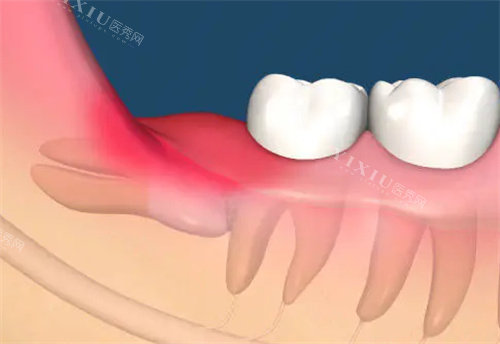

没过多久,就轮到我看诊了。给我看诊的是一位经验充足的医生,他先是详细地询问了我的症状和病史,然后让我去拍了牙片。拍完牙片回来,医生拿着片子给我仔细地讲解了智齿的情况,告诉我这颗智齿长歪了,顶到了旁边的牙齿,所以才会经常发炎疼痛,必须得拔掉。他还跟我说明了拔牙的流程和可能会出现的风险,让我心里有了底。